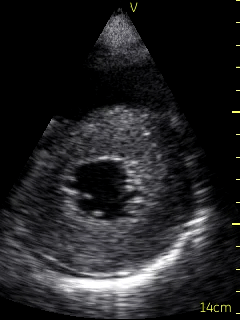

A bedside echocardiogram (VScan, GE) showed evidence of severe left ventricular and right ventricular thickening. Both atria were severely dilated. The mitral, tricuspid, and aortic valves appeared thickened. Myocardial speckling was not appreciated. Both the left and right ventricular function appeared to be moderately impaired.